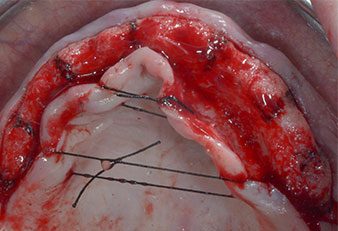

Drei Jahre später war es Zeit für eine gleichartige Oberkieferprothese. Basierend auf der DVT-Planung wurde durch Verwendung kurzer Implantate eine Sinusaugmentation vermieden und die geplanten Implantatpositionen wurden mit einer Bohrschablone auf den Kieferkamm übertragen (Abb. 1 und 2).

Ein flammenförmiges, diamantiertes piezochirurgisches Instrument (Piezomed I1) wurde verwendet, um die Implantatpositionen zu markieren und die Pilotpräparationen durchzuführen (Abb. 3). Dabei wurde darauf geachtet, eine Auf- und Abbewegung mit reduzierter Leistung, voller Spülung und niedrigem Druck (unter 300 g) anzuwenden. Als Nächstes wurde ein Pilotinstrument (Piezomed I2A/I2P) zur initialen Erweiterung der Implantatlager auf einen Durchmesser von 2 mm verwendet (Abb. 4), gefolgt von einem 3-mm-Instrument (Abb. 5).